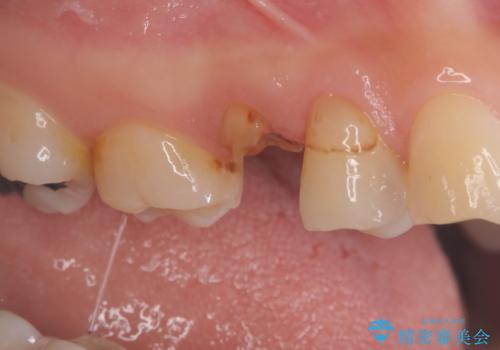

- 定期検診にて不良補綴物、及び虫歯を認めオールセラミッククラウンにて治療を行いました。

右上第二小臼歯はカリエス除去中に露髄を認め、部分的断髄法にて歯髄を保存しております。